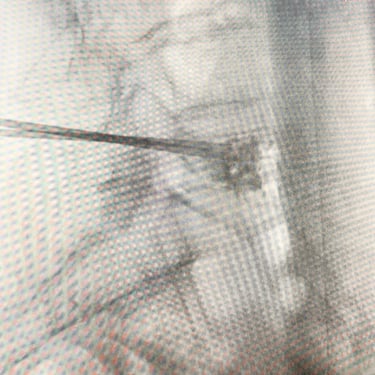

🧠Fractura vertebral lumbar osteoporótica en el adulto mayor: manejo con vertebroplastia percutánea.

Las fracturas vertebrales osteoporóticas en adultos mayores son una causa frecuente de dolor lumbar incapacitante. La vertebroplastia percutánea es un procedimiento mínimamente invasivo que permite estabilizar la vértebra afectada mediante la inyección de cemento óseo, logrando alivio del dolor y recuperación funcional temprana en pacientes seleccionados.